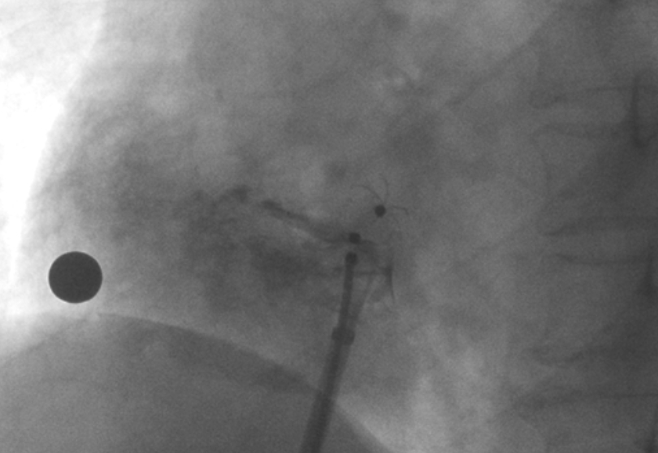

术中造影显示患者为PFO且长隧道型,目前市场上已商业化的PFO封堵器难以满足该患者解剖结构封堵需求。迪创医疗自主研发的OmniSeal PFO封堵器自适应性双盘贴合设计能广泛适应不同PFO隧道长度的解剖结构和形态,其双盘外包覆式阻流和隧道内填充阻流相结合的双重阻流设计,可为此患者实现有效封堵。与此同时,OmniSeal首创的完全可穿刺式设计,也为此患者最大程度地保留了房间隔区域穿刺通道,以实现全兼容未来可能的左心系统二次介入术。术终造影和心脏超声显示封堵完全、效果良好。作为OmniSeal的首例临床应用,本次手术的顺利完成和优异效果充分体现了产品的设计创新优势。

造影显示PFO封堵完全,无残余分流,

试验器械充分舒展并贴合良好